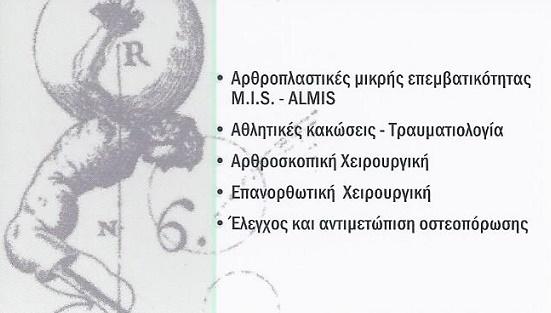

Αρθοπλαστικές Χαλάνδρι, Επανορθωτική χειρουργική Χαλάνδρι